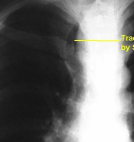

substernal goiter

trachea displaced